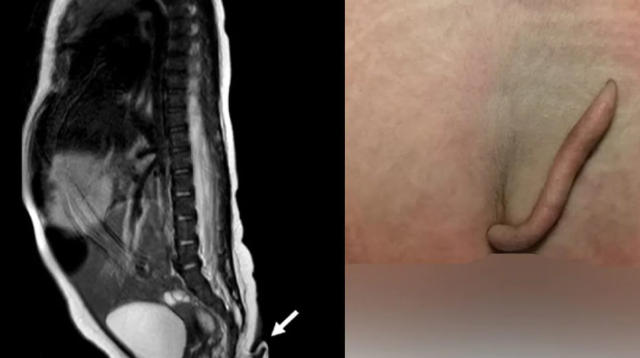

Bambina con coda (fonte Journal of Pediatric Surgery Case Reports)

L'appendice della bambina era lunga precisamente 5,7 centimetri. Rimossa attraverso la resezione chirurgica, è stato poi analizzata, portando i medici ad una scoperta inaspettata. La coda non presentava tessuto osseo al suo interno, ma solo pelle, muscoli, nervi, tessuto connettivo, vasi sanguigni e grasso. Il diametro era di circa 3 – 5 millimetri e aveva una struttura generalmente cilindrica, più spessa all'apice e con un terminale appuntito.

A descrivere il caso della bimba messicana nata con la coda è stato un team guidato da medici e ricercatori del Dipartimento di Chirurgia Generale dell'Azienda Ospedaliera Universitaria “Dr. José Eleuterio González” – Università Autonoma di Nuevo León. Il gruppo ha collaborato a stretto contatto con i colleghi del Reparto di Pediatria. Gli specialisti, coordinati dal professor Gerardo Munoz, hanno scoperto la coda solo dopo la nascita della bambina, avvenuta tramite parto cesareo. L'appendice era lunga circa 6 centimetri e si presentava ricoperta di peli e pelle, senza ossa all'interno.

La piccola è nata perfettamente in salute, senza disfunzioni o malformazioni agli organi. Anche il punteggio Apgar – una scala che rileva se un neonato è sano e vitale – era pienamente nella norma. L'unica anomalia era rappresentata dalla coda, che i medici hanno monitorato per alcune settimane prima di procedere alla resezione chirurgica. Il taglio è stato effettuato a poco più di due mesi dal parto. La coda era cresciuta di altri 0,8 centimetri. Durante l'operazione è stata eseguita una ricostruzione di Limberg, utilizzando tessuto prelevato dalle natiche.